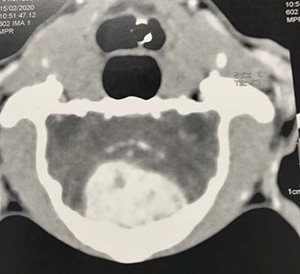

Nous effectuons de la chirurgie intra crânienne pour le traitement des tumeurs cérébrales

cerveau 1 cerveau 2